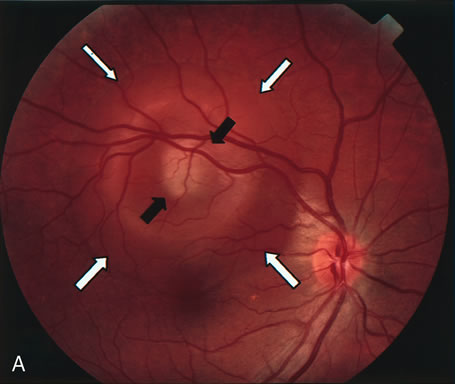

FA is also useful in characterizing two other subgroups of CNV: retinal angiomatous proliferation (RAP)8–16 and polypoidal choroidal vasculopathy (PCV).17–50 RAP begins in the deep retinal complex, forming intraretinal neovascularization (IRN), which may subsequently progress to extend beneath the neurosensory retina, forming subretinal neovascularization (SRN), and a vascularized PED.8 In the later phases of the process there may be a retinal-choroidal anastomosis (RCA). Clinical features of RAP include intraretinal hemorrhages, cystoid macular edema, and associated vascularized PED. FA is useful in revealing the presence of the angiomatous intraretinal vascular complex and the extension of the associated PED (Figs. 12 and 13). However, other diagnostic techniques such as indocyanine green (ICG) angiography, and optical coherence tomography (OCT) may be able to better demonstrate the presence of the RAP lesion.

Fig. 12. A. Clinical photograph of a retinal angiomatous proliferation (RAP) lesion (arrow). Note the intraretinal angiomatous proliferation, a feeding retinal arteriole, and a draining retinal venule, as well as the presence of intraretinal hemorrhages. B–C. Fluorescein angiography reveals late leakage from the RAP lesion.